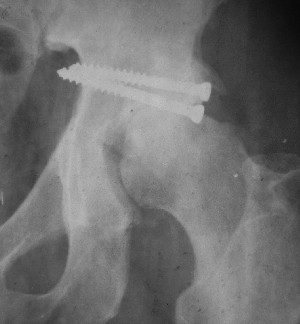

После протезирования прямой 5/04/04

|

После протезирования боковой 5/04/04

Больной 18 мая 2003 года в автоаварии получил перелом левой вертлужной впадины, вывих бедра. Госпитализирован в один из стационаров области.Вывих вправлен. В последствии бедро вывихивалось еще дважды. На консультацию был представлен снимок от 19.05.03г., больной переведен к нам 3.06.03г. Снимок при поступлении - перелом впадины, задне-верхний вывих бедра. 05.06.2003 г. выполнено открытое вправление вывиха левого бедра и остеосинтез стенки вертлужной впадины двумя винтами. Послеоперационный период без осложнений. Объем движений в левом тазобедренном суставе восстановился полностью. Выписан на амбулаторное лечение в удовлетворительном состоянии с рекомендациями 3 месяца ходить на костылях без нагрузки на оперированную конечность. На контрольных рентгенограммах левого тазобедренного сустава 13.10.2003 г. - признаки консолидации перелома; плотность, форма головки и состояние суставных поверхностей удовлетворительные. Разрешена дозированная осевая нагрузка, на конечность с использованием дополнительной опоры. 19.12.2003 г. больной обратился с жалобами на боли в левом тазобедренном суставе. На рентгенограммах левого тазобедренного сустава 19.12.2003 г., 20.02.04г. - асептичекий некроз головки бедра. 5.04.04г. - эндопротез. Сейчас ходит без трости, не хромает. Особенность эндопротезирования - при удалении винтов прослежена линия перелома заднего края впадины и предложено установить чашку несколько меньшего диаметра, чтобы она была покрыта несломанной частью.